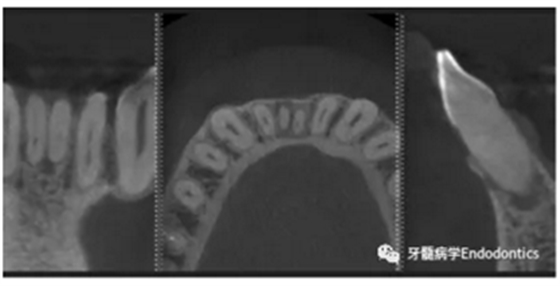

31、41叩痛明顯,牙冠變色(圖1)。溫度和牙髓電活力測(cè)試無(wú)反應(yīng)。兩張從不同角度拍攝的x線(xiàn)片顯示,相對(duì)于側(cè)切牙,雙側(cè)下中切牙都有嚴(yán)重的根管鈣化(圖2)。41有明顯根尖周暗影,31根尖周暗影不明顯。為進(jìn)一步證實(shí)31是否存在根尖周病變,同時(shí)精細(xì)觀(guān)察31、41的復(fù)雜結(jié)構(gòu),根據(jù)歐洲牙髓病學(xué)會(huì)CBCT應(yīng)用指南(2014),對(duì)患牙拍攝小視野、高分辨率CBCT。CBCT影像證實(shí)31、41均伴有根尖周炎和嚴(yán)重的根管鈣化(圖3)。距離根尖4mm可見(jiàn)根管影像。 由于患牙根管解剖結(jié)構(gòu)較為復(fù)雜,筆者決定使用特殊設(shè)計(jì)的微型鉆頭(直徑0.85mm)進(jìn)行“數(shù)字化導(dǎo)航牙髓治療”。 因此對(duì)下頜進(jìn)行口內(nèi)掃描(圖4)。用coDiagnostixTM軟件(Dental Wings Inc.,Montreal,Canada)將CBCT和口內(nèi)掃描的數(shù)據(jù)進(jìn)行處理,該軟件主要用于引導(dǎo)種植。通過(guò)該軟件對(duì)兩個(gè)掃描圖像進(jìn)行疊加后,虛擬鉆頭尖端沿牙長(zhǎng)軸對(duì)準(zhǔn)根管下段可見(jiàn)部分(圖5)。三維檢查虛擬鉆的正確位置。

圖3.下頜前牙CBCT影像。